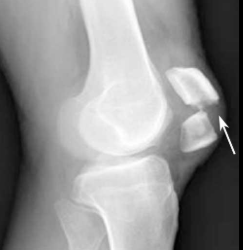

X-ray(방사선 촬영): 뼈의 정렬 이상, 관절 간격 변화, 골극 형성 등 연골 이상을 간접적으로 시사하는 변화가 있는지 살핍니다. 하지만 연골 자체는 잘 보이지 않아 조기 진단이나 경미한 연화증에서는 한계가 있습니다.